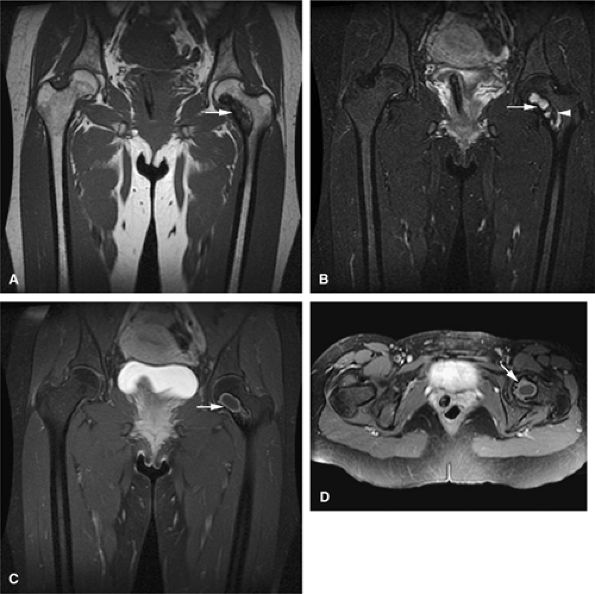

FIGURE 14-5 ● FDG-PET in the evaluation of patients with sarcomas. Whole-body FDG-PET scan (A) and corresponding axial image (B) in a patient with neurofibromatosis type 1 demonstrates a region of intense FDG uptake in the right buttock area (arrow), which was found to represent a malignant peripheral nerve sheath tumor arising in a neurofibroma. (C and D) Images from a whole-body FDG PET scan in a patient with osteosarcoma show intense FDG uptake in the proximal tibia (D) in the area of the tumor (arrow). Images of the chest and abdomen demonstrate no evidence of metastatic disease. A marker was placed over the left chest wall (C) (arrowhead). (E) Coronal, axial, and sagittal images of a whole-body FDG-PET scan in a patient with osteosarcoma of the right femur. The patient underwent resection of the right femur and total knee arthroplasty. MR images and CT scans were deemed inadequate for tumor evaluation because of metallic artifact. FDG-PET scan shows a cold defect in the region of the right knee arthroplasty (arrows) and no increased FDG uptake in the area of the right femur and knee.